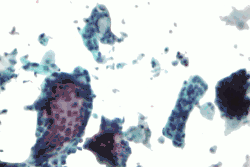

Od tego czasu FNAB pozostaje podstawową i najtańszą metodą diagnostyki zmian litych gruczołu sutkowego. Nakłucie wykonuje się igłą wielkości 27-21 G (0,4-0,8 mm średnicy)[9][10] przyłączoną do strzykawki o obj. 20 ml. Pociągnięcie za tłok pozwala zassać materiał płynny i/lub złuszczone komórki. Aspirat rozmazuje się na szkiełku mikroskopowym i konserwuje w celu uzyskania preparatu cytologicznego.

FNAB jest metodą z wyboru, jeżeli wykryta masa ma charakter torbielowaty. Całkowite usunięcie płynu, który nie zawiera domieszek krwi, świadczy o łagodnym charakterze zmiany. Biopsję cienkoigłową wykorzystuje się również do pobierania fragmentów pachowych węzłów chłonnych w celu wykluczenia przerzutów. W tym wypadku wystarczy wykrycie pojedynczych komórek nowotworowych, aby stwierdzić postęp choroby[11]. W przyszłości metody molekularne powinny pozwolić na szczegółową charakterystykę zmian złośliwych nawet na podstawie tak skąpej ilości materiału, jaką pozyskuje się za pomocą FNAB [51-53]

Ograniczona skuteczność badania nie pozwala, aby o chorobie nowotworowej orzekać wyłącznie na podstawie jego wyniku. Odsetek wyników fałszywie ujemnych wynosiłby wówczas 25–50%[12][13], a fałszywie dodatnich do 9%[14][13]. Duża liczba próbek nie przedstawia wartości diagnostycznej: od 8,5–26,6% w wypadku nakłucia pod kontrolą USG czy próbkowania litych mas do 46,1% przy dochodzeniu przyczyny mikrozwapnień[2]. Ostateczna jakość wyniku silnie zależy od doświadczenia i dostępności ekipy cytopatologicznej[15][16]. W Stanach Zjednoczonych wyniki fałszywie dodatnie mogą narazić lekarza na zarzuty "niekompetencji" i stać się przyczyną późniejszych pozwów sądowych[17].